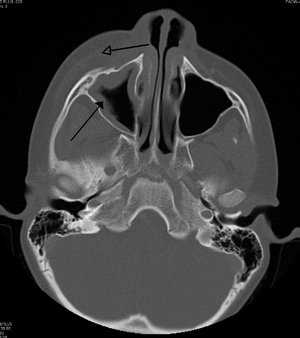

التهاب الهلل حول الحجاج الناجم عن عدوى بالأسنان (تسبب أيضًا التهاب الجيوب الأنفية)

يجب التمييز بين التهاب الهلل حول الحجاج والتهاب الهلل المحجري ، وهو حالة طارئة ويتطلب مضادات حيوية عن طريق الوريد (IV). على عكس التهاب الهلل المحجري ، لا يعاني المرضى المصابون بالتهاب الهلل حول الحجاج من انتفاخ في العين ( جحوظ العين ) ، أو حركة محدودة للعين ( شلل في العين ) ، أو ألم في حركة العين ، أو فقدان الرؤية. في حالة وجود أي من هذه الأعراض ، يجب على المرء أن يفترض أن المريض يعاني من التهاب الهلل المحجري ويبدأ العلاج بالمضادات الحيوية الوريدية. يمكن إجراء الفحص بالأشعة المقطعية لتحديد امتداد العدوى.

تشمل الاختبارات تحاليل الدم (CBC) لاستبعاد السبب المعدي. قم أيضًا بإجراء فحص بالأشعة المقطعية والأشعة السينية للجمجمة الأمامية لعرض الجيوب الأنفية ومسح التصوير بالرنين المغناطيسي وأخيراً الموجات فوق الصوتية للأنسجة الرخوة في المنطقة الحجاجية